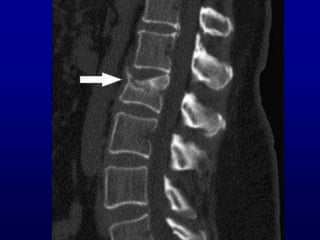

Da non dimenticare

Sublussazione di C1 su C2

L’AR puo’ causare un’instabilita’ asintomatica del collo

La manipolazione durante sedazione puo’ causare una lesion midollare